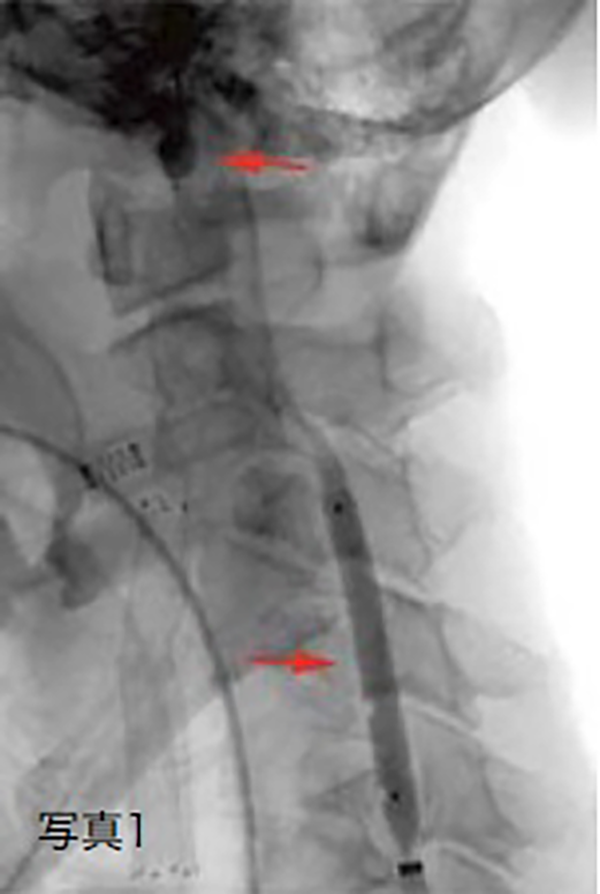

(写真1)は前拡張を行っているところです。前拡張後ステントを留置し、遮断された血液中の血栓やコレステロールのカスは風船と交換された血栓吸引用の細いカテーテルで吸引します。

これで血管の中がきれいになった状態ではじめて小さな風船あるいはフィルターを解除して終了です。必要に応じて後拡張を行います。(写真2)